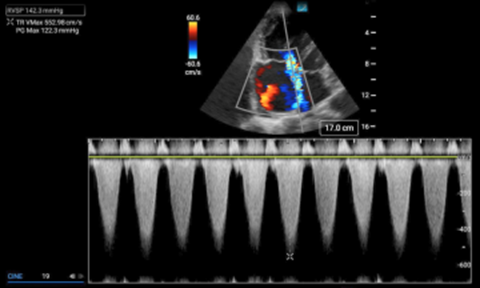

Calculating right ventricular systolic pressure

The right ventricular systolic pressure (RVSP) determined by echocardiography can approximate the pulmonary artery systolic pressure (assuming a normal pulmonic valve). Determining this value is predicated on the ability to measure the velocity of the tricuspid regurgitant jet in an apical four chamber view. To obtain this value, the tricuspid regurgitant jet is first identified in an apical four chamber view (A4C) using color doppler. The eccentric jet shown in Figure 1 highlights the importance of first localizing it with color doppler. Then a continuous wave (CW) doppler line is placed through that jet with the focal zone (diamond) in or near the vena contracta (the thinnest part of the jet close to the valve). The resulting wave form should demonstrate repeating downward parabolas. (Figure 1) Increasing the doppler scale, and adjusting the baseline upwards, may be necessary to avoid aliasing for these high velocity cases. The pressure gradient is then extrapolated by using a simplified Bernoulli equation. In the case of this patient, the velocity measures 5.53 m/s, so the pressure gradient (PG) is about 122mmHg (normal would be zero to trace regurgitation). In cases where the diagnosis of PAH is known, comparing the patient’s historic RVSP value to that on presentation, can be helpful.

Simplified Bernoulli Equation

Tricuspid Valve Regurgitant Jet Pressure Gradient (PG) = 4V2

PG = 4 (5.53)2 = 122.3 mmHg

Figure 1. Continuous wave doppler measuring the maximum velocity of the tricuspid regurgitant jet (TR Vmax).